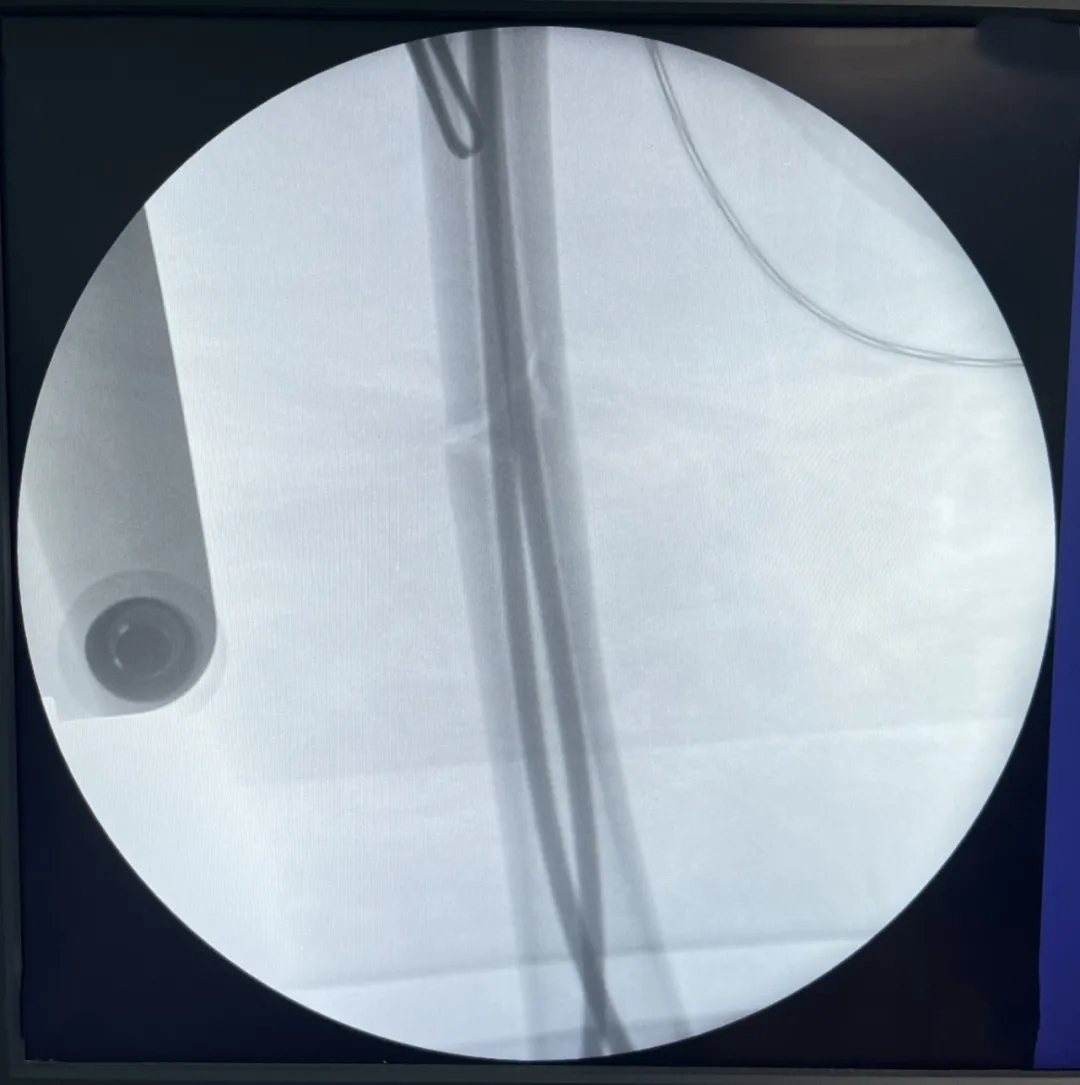

經(jīng)與家長(zhǎng)詳細(xì)溝通,我院骨科專家團(tuán)隊(duì)決定為患兒實(shí)施右股骨干骨折閉合復(fù)位彈性髓內(nèi)釘內(nèi)固定手術(shù)。術(shù)中,顧署光主任及趙飛副主任醫(yī)師在團(tuán)隊(duì)專家及手術(shù)室、麻醉科醫(yī)護(hù)人員的配合下,憑借精湛的醫(yī)術(shù)與熟練的操作手法,在樂樂患肢內(nèi)外兩側(cè)開了2個(gè)不足2cm小切口,對(duì)稱插入兩根彈性髓內(nèi)針,利用鈦合金或不銹鋼良好的彈性恢復(fù)力作用于骨骼,通過髓腔的3個(gè)接觸點(diǎn)轉(zhuǎn)換成推力和壓力,從而使骨折復(fù)位。手術(shù)成功,目前樂樂恢復(fù)良好。

內(nèi)外側(cè)兩個(gè)小切口